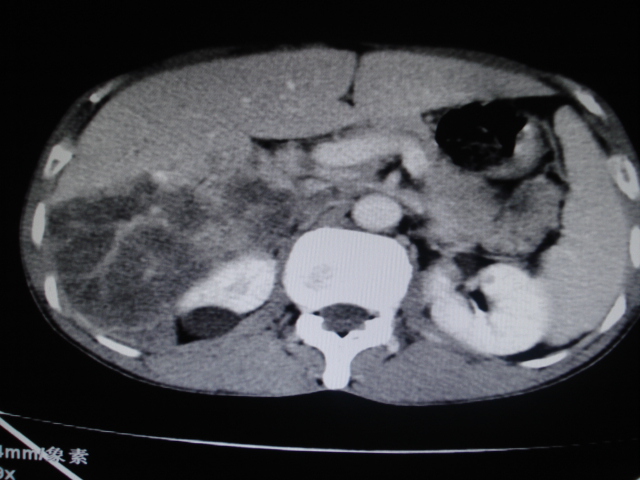

标题: CT24041:肝脏占位,请会诊!

男性,62岁。肝右叶占位,平扫及增强如下,延迟期为15分钟扫描。

给病史及实验室检查!多考虑胆管细胞癌;右肾囊肿。

1)不均匀性脂肪肝。2)肝硬化。3)肝右叶肝癌不排除。4)右肾囊肿。